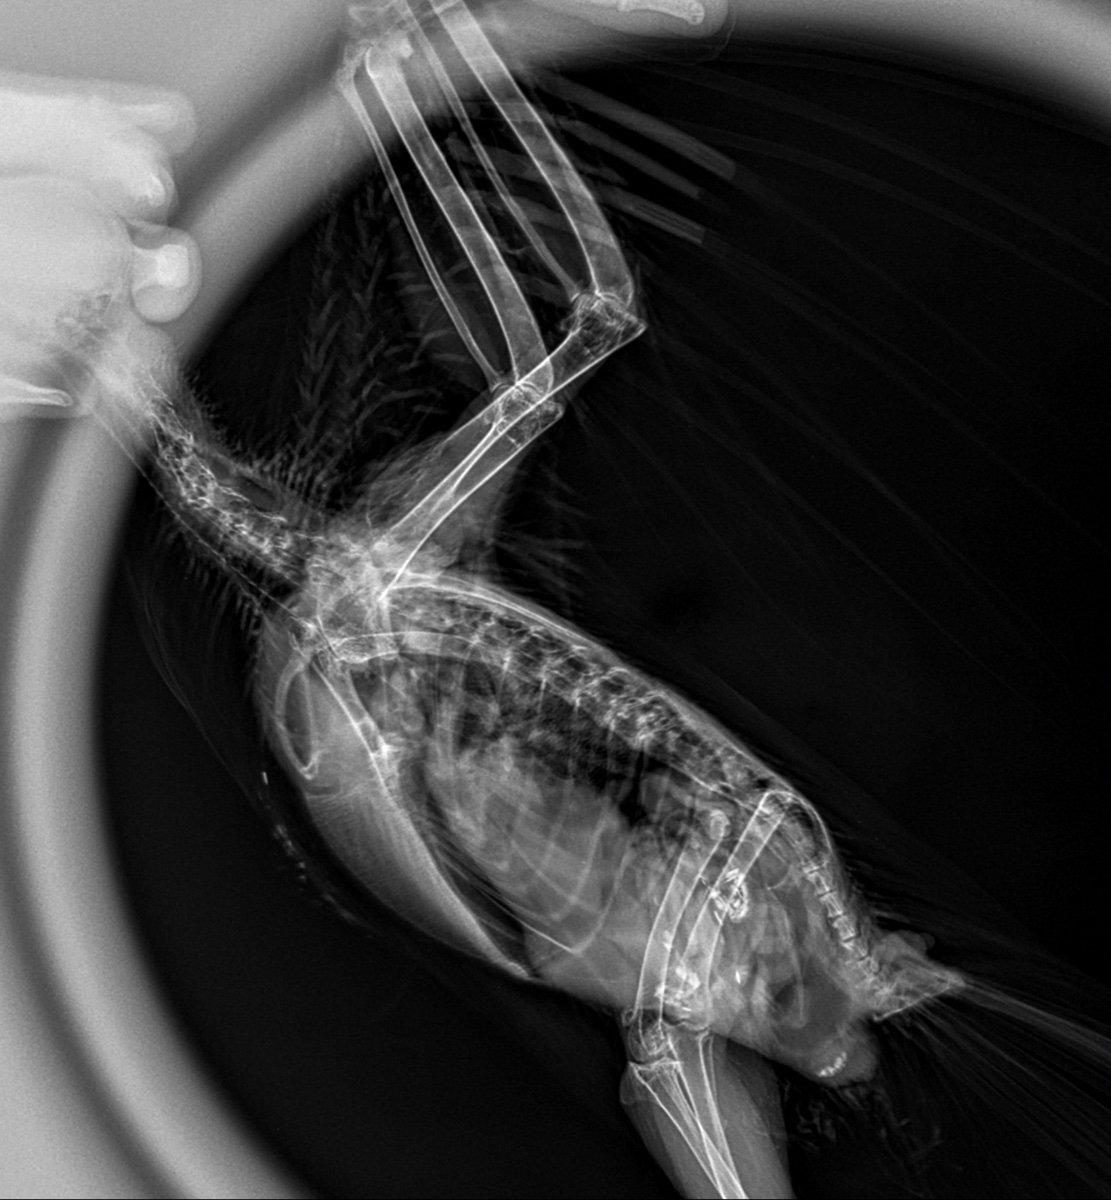

Серая ворона Геша, 12 лет. Был подобран маленьким птенцом. Никогда не болел. Живет в вольере на улице. Выкармливали и растили благодаря форуму по врановым на mybirds. Сейчас заканчивает линьку. Позавчера утром обнаружили его лежащим на животе с распластанными крыльями. Стоять не может. Лапки висят и не реагируют ни на что. Аппетит плохой, съел только немного промороженных насекомых. Были в клинике. Сделали рентген. Получили заключение и рекомендации, но мучают сомнения:( Птице очень плохо. Может специалисты посмотрят наши снимки🙏

E104C390-EF90-44CD-BF48-0376CF3E676C.jpeg

03F9A086-38BB-4609-9283-E09C83A7C715.jpeg

C3D20BF0-AF12-43C6-9388-E6DCDD44A749.jpeg

6572F185-2473-4DD0-8AC5-725CE4A319CE.jpeg

Нижний снимок голубя. Для срочного ответа пишите Zosia по Вацапу.